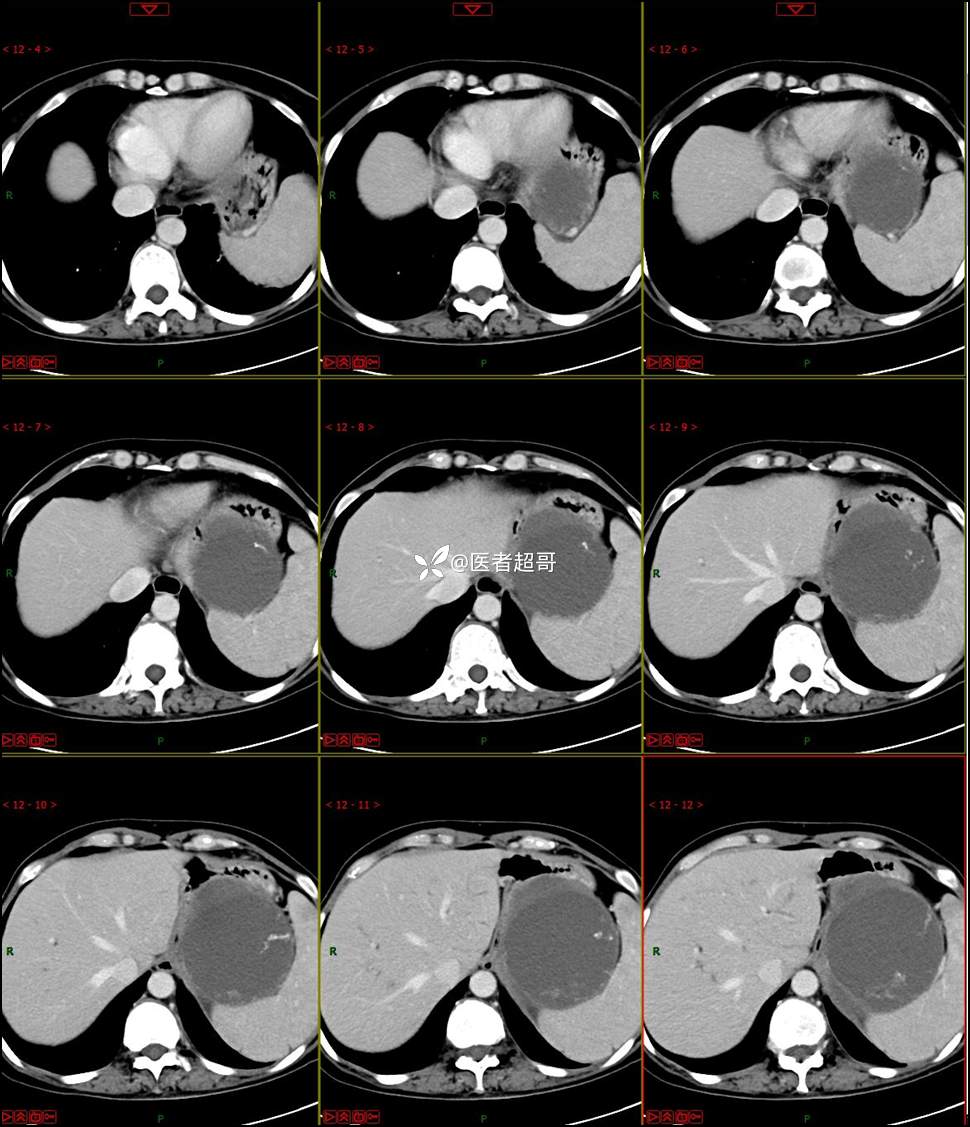

【影诊笔记768】肾脏肿瘤?肾上腺肿瘤?请诊断分析!

女 57岁 0200908 01

主 诉:发现左肾肿物7月余

现病史:患者7月前因左侧腹部疼痛不适,就诊市人民医院,行CT平扫:左侧肾上腺区混杂密度肿块,考虑肿瘤合并出血,行保守治疗后症状缓解出院,左侧下腹部及左侧髋部疼痛不适,无尿频、尿急、尿痛,无肉眼血尿,无寒战、发热,今患者为求进一步诊治,就诊我院,门诊以“左肾肿物”为诊断收入院,患者自发病以来,神志清,精神可,饮食睡眠可,小便如上述,大便正常,体重未见明显改变。